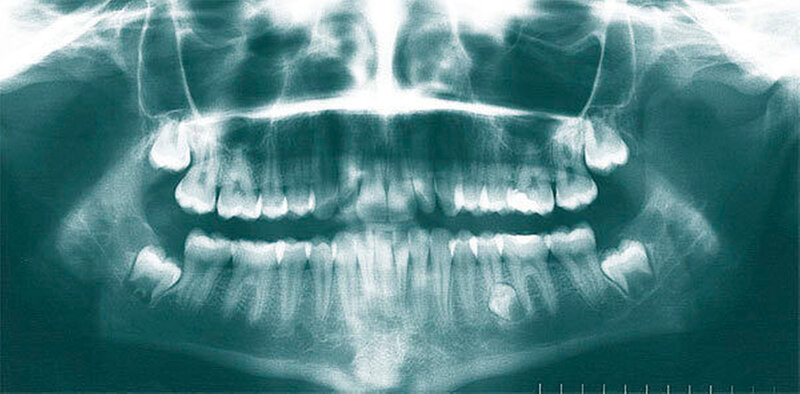

Überzählige Zähne können einzeln oder multipel auftreten [von Arx, 1990; Rajab Hamdan, 2002; Fernández Montenegro et al., 2006; Liu et al., 2007; Gündüz et al., 2008; Ferrés-Padró et al., 2009; Hyun et al., 2009]. Einzelne überzählige Zähne treten in 65,8 bis 80,5 Prozent, doppelte in 14,5 bis 27,7 Prozent und multiple in 0,6 bis 8 Prozent der Fälle auf [Rajab Hamdan, 2002; Fernández Montenegro et al., 2006; Liu et al., 2007; Ferrés-Padró et al., 2009; Hyun et al, 2009; Mossaz et al., 2014]. Einzelne oder doppelte überzählige Zähne finden sich typischerweise in der Oberkieferfront [Rajab Hamdan, 2002; Fernández Montenegroet al., 2006; Mossaz et al., 2014]. Multiple überzählige Zähne werden vor allem im Prämolarenbereich des Unterkiefers gefunden [Abbildung 4; YUSOF 1990, Ferrés-Padróet al., 2009; Wang Fan, 2011]. Multiple überzählige Zähne sind zudem oft mit anderen Erkrankungen oder Syndromen assoziiert, dazu gehören Lippen-Kiefer-Gaumenspalten, die cleidokraniale Dysplasie oder auch das Gardner-Syndrom. Bei Patienten mit einer Lippen-Kiefer-Gaumenspalte wird vermutet, dass sich die überzähligen Zähne aus der Fragmentierung der dentalen Lamina bei der Spaltbildung ergeben [Garvey et al., 1999; Wang Fan, 2011].

Überzählige Zähne werden nach ihrer Lage im Zahnbogen und auch aufgrund ihrer Morphologie eingeteilt. Basierend auf der Lage unterscheidet man bei überzähligen Zähnen zwischen Mesiodens (Oberkiefer median), zwischen den zentralen Inzisiven (Abbildungen 5 und 6), einem zusätzlichen Schneidezahn (zentral oder lateral), Eckzahn, Prämolar (Abbildung 7), Paramolar und Distomolar (Abbildungen 8). Mesiodentes werden am häufigsten dia- gnostiziert, wobei Prozentsätze zwischen 38,8 Prozent bis 86,3 Prozent der überzähligen Zähne in der Literatur zu finden sind [Salcido-García et al., 2004/38,8 Prozent, Fernández Montenegro et al., 2006 /46.9 Prozent; Mossaz et al., 2014/48.5 Prozent; Ferrés-Padró et al., 2009/53.2 Prozent; Schmuckli et al., 2010/75 Prozent; Rajab Hamdan 2002/83.2 Prozent; Liu et al., 2007/86.3 Prozent]. Überzählige Prämolaren und seitliche Schneidezähne sind die zweithäufigste Gruppe der überzähligen Zähne. Überzählige Eckzähne, Paramolaren und Distomolaren dagegen gelten als eher selten [Rajab Hamdan, 2002; Salcido- García et al., 2004; Liu et al., 2007; Ferrés-Padró et al., 2009; Schmuckli et al., 2010; Mossaz et al., 2014]. Einzig eine Spanische Gruppe [Fernández Montenegro et. al., 2006] berichtete, dass Paramolaren und Distomolaren insgesamt relativ häufig seien (18 Prozent, beziehungsweise 5,6 Prozent). Überzählige Zähne kommen im Ober- und Unterkiefer vor, wobei sich überzählige Schneidezähne in der Regel im Oberkiefer, überzählige Prämolaren sich dagegen eher im Unterkiefer befinden [Fernández Montenegro et al., 2006; Ferrés-Padró et al., 2009; Mossaz et al., 2014]. Überzählige Molaren wiederum treten normalerweise im Oberkiefer auf [Cassetta et al., 2014; Kaya et al., 2014].